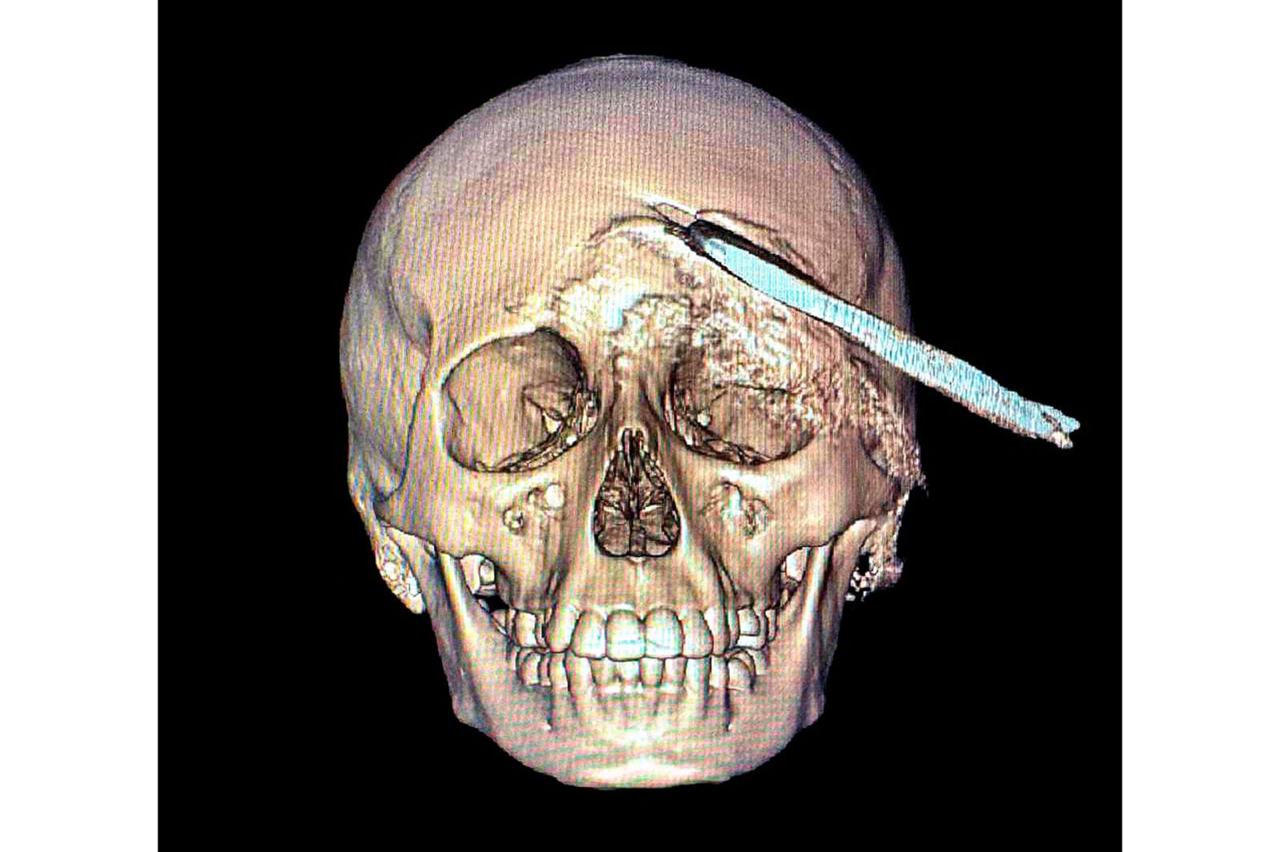

El Instituto Mexicano del Seguro Social (IMSS) en Yucatán logró un hecho médico sin precedentes al retirar, mediante una compleja cirugía, una herramienta agrícola -coa- de aproximadamente 30 centímetros incrustada en el cráneo de un adolescente de 15 años, procedimiento que permitió salvarle la vida.

El 2 de noviembre, Yael fue trasladado desde el municipio de Acanceh al Hospital General Regional (HGR) No. 12 del IMSS en Mérida, donde la directora, doctora Claudia González Ramírez, y un equipo de especialistas ya se encontraban preparados para recibirlo y atender la emergencia. Tras confirmarse un traumatismo craneoencefálico severo, se realizaron estudios inmediatos que determinaron la profundidad y ubicación del objeto.

Ante la complejidad del caso, el neurocirujano Elías Sinahí Ramírez Sánchez determinó que el adolescente debía ser trasladado al HGR No. 1, que cuenta con el equipo necesario para una intervención especializada.

La jefa de Pediatría del HGR No. 1, doctora Ana Isabel Velázquez Ibarra, informó que este es el primer caso pediátrico en el estado con esta clase de lesión. Al ingreso del paciente, el equipo médico lo estabilizó y, en coordinación con el neurocirujano Luis Víctor Ornelas González, se diseñó el protocolo de atención para garantizar su seguridad durante la cirugía.

Los estudios de imagen permitieron ubicar con precisión el objeto, mientras que el menor recibía tratamiento con antibióticos de amplio espectro para prevenir infecciones asociadas con el instrumento metálico.

Después de un análisis minucioso y una planeación quirúrgica, el doctor Ornelas González dirigió un procedimiento de cuatro horas que permitió retirar exitosamente el machete curvo sin afectar tejido cerebral, en una intervención que confirmó la pericia y capacidad del equipo médico.